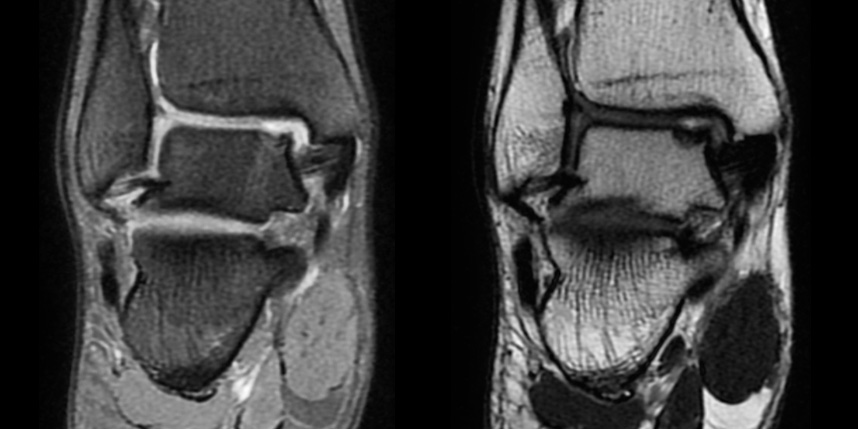

타병원 미세천공술 실패 후 통증으로 내원하신 사례

* 환자에게 받은 소중한 자료입니다.